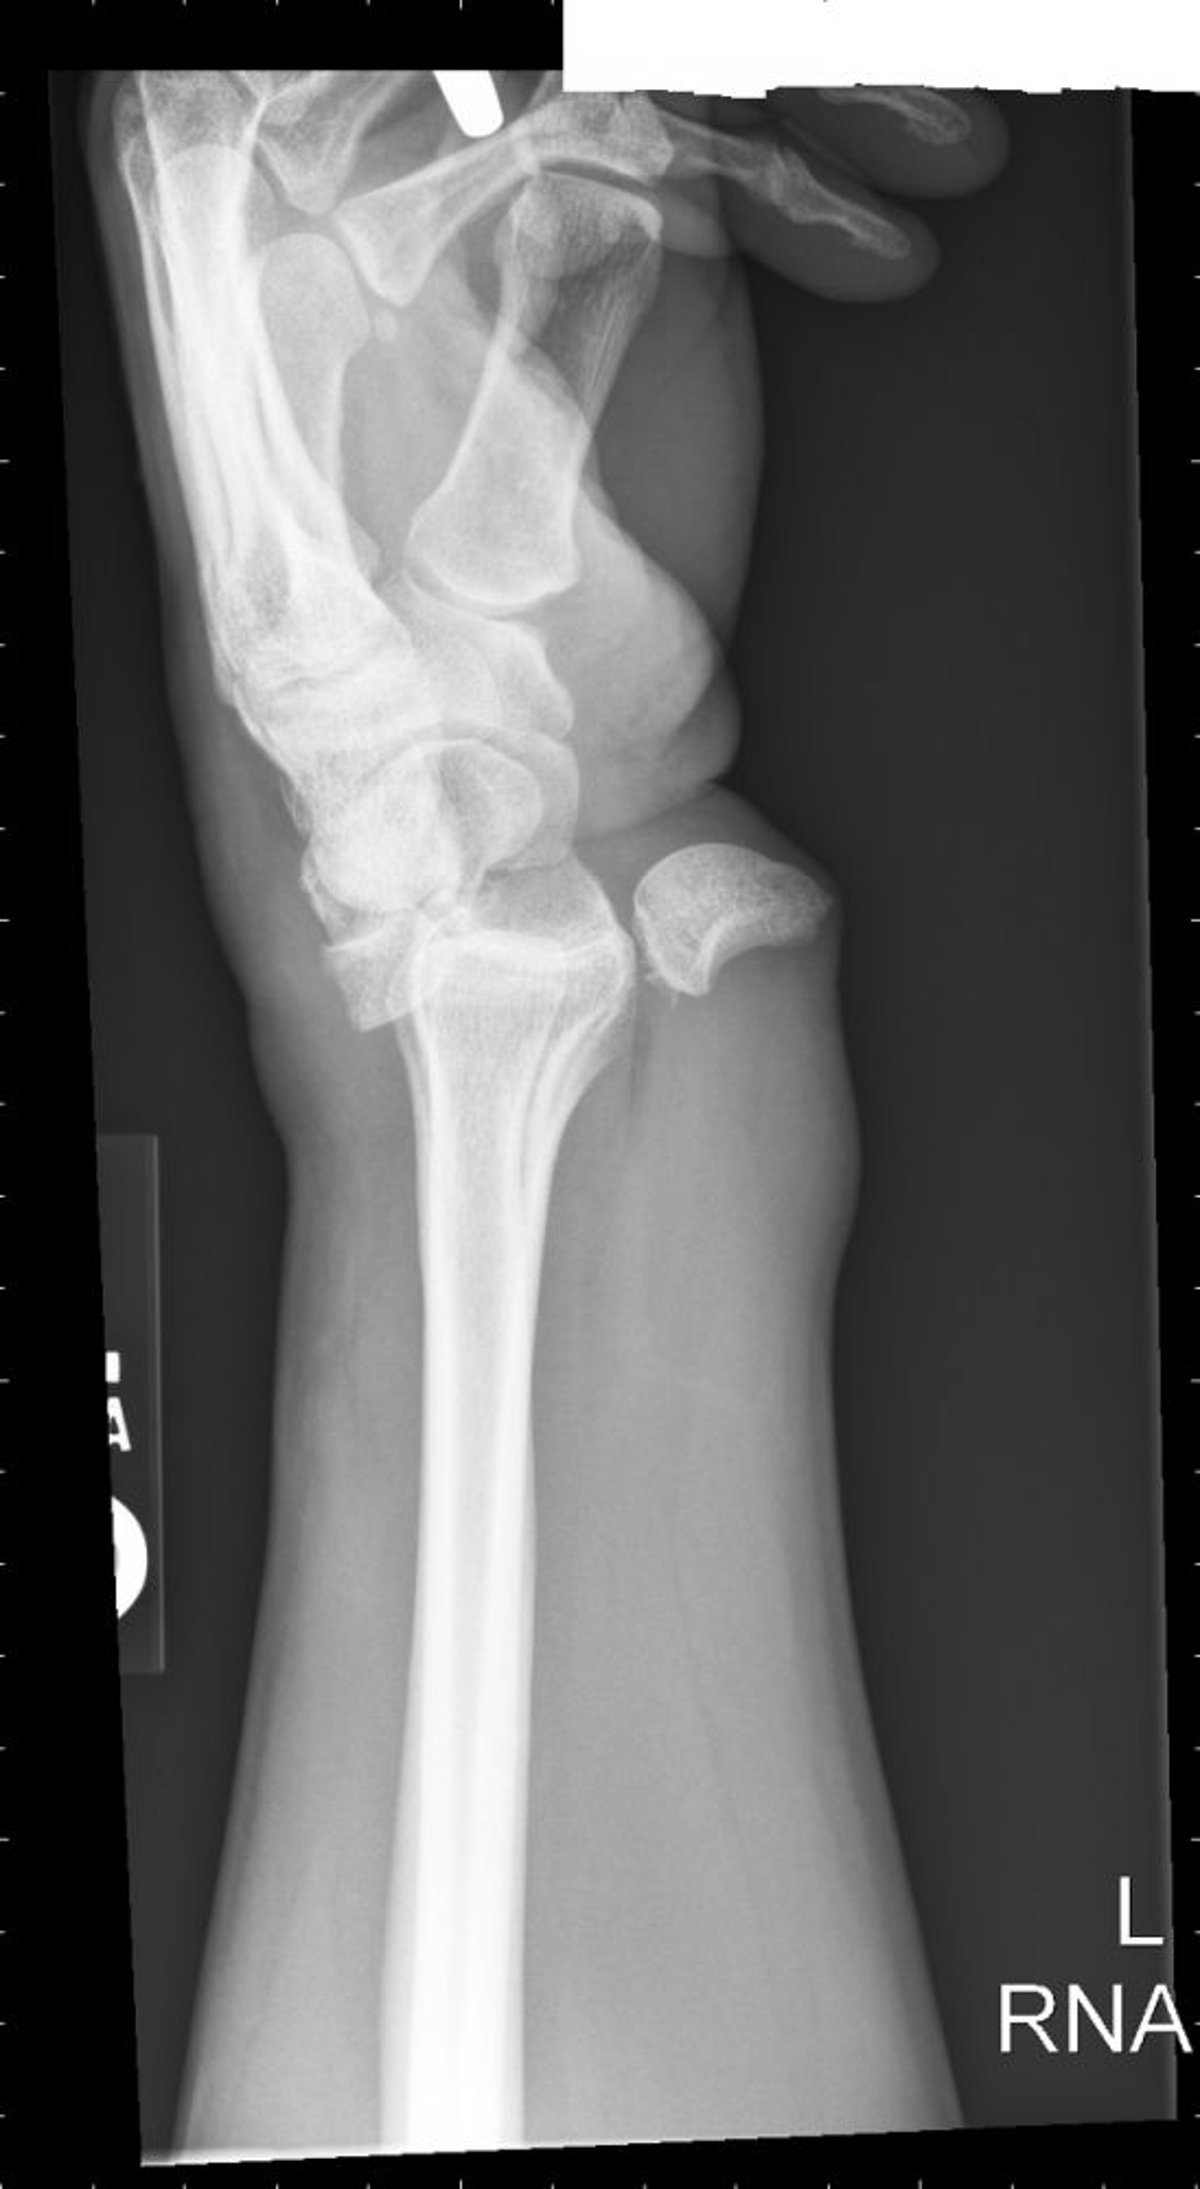

Trật khớp xương nguyệt

Trật khớp xương nguyệt dẫn hình ảnh tách trà.

Hình ảnh do bác sĩ Danielle Campagne cung cấp.